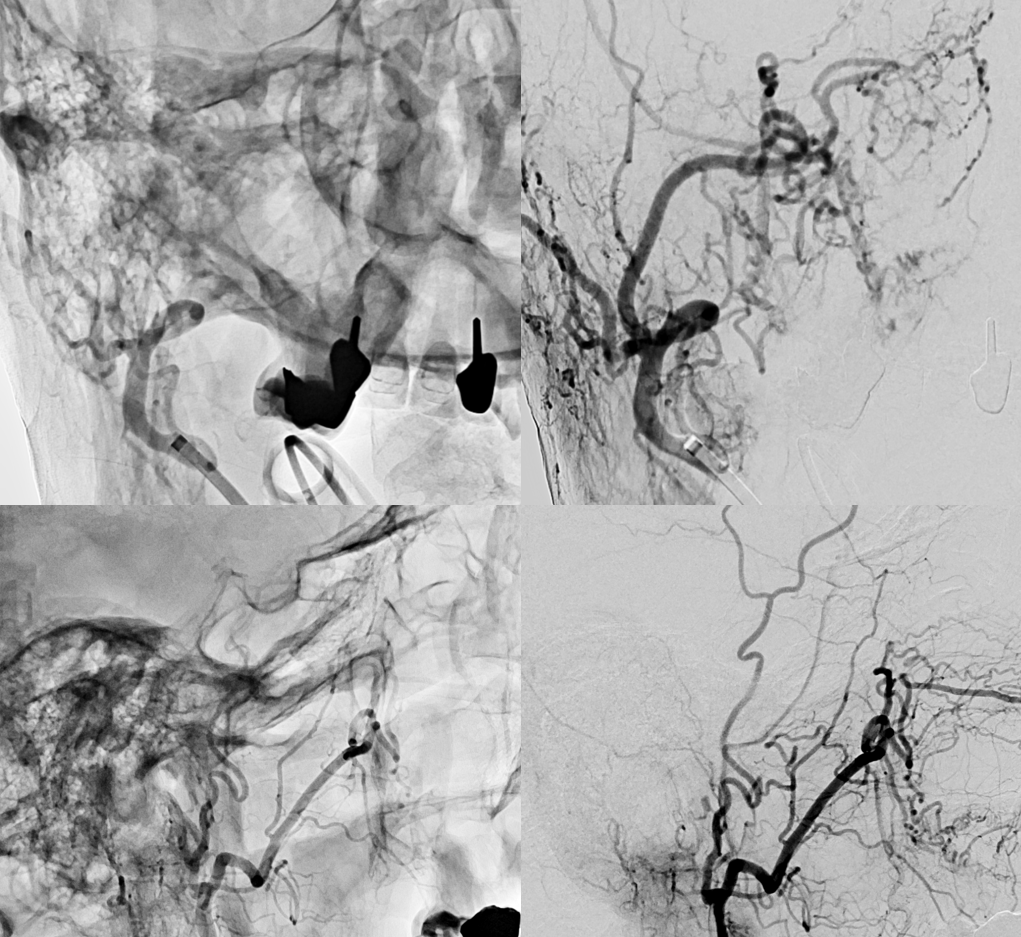

There are a number of options present here. One is to try to recanalize the MMA — the advantage is that if it does not work out, nothing bad happens.

Recanalization is successful with Aristotle 14 standard and headway duo, supported by Phenom Plus and Benchmark (radial access)

The rest of the way is not easy either — tons of tortuosity. This is addressed with a hybrid .07, and phenom plus in the MMA beyond the recanalized occlusion. Amazing

Onyx

It is important to have control from other side — and another access for that. Needed more onyx